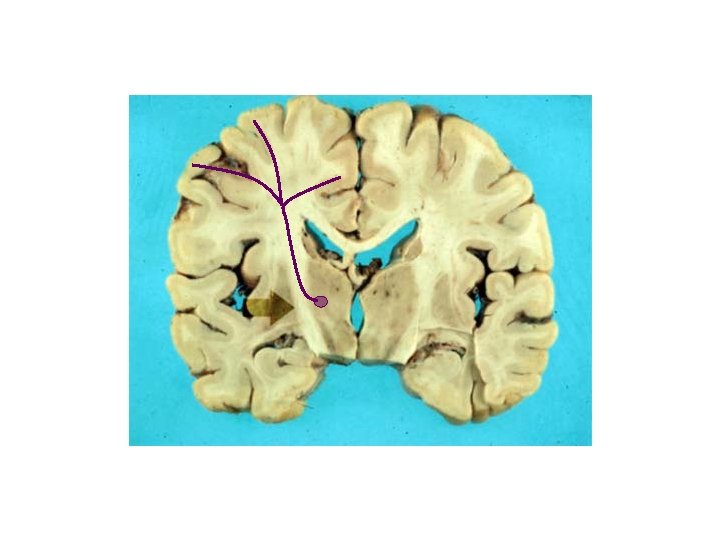

The yellow represents area of a lesion. What sensory loss would you expect? R L

The yellow represents area of a lesion. What sensory loss would you expect? L R Below the lesion: • Loss of pain and temp from left side • Loss of proprioception/vibration from right side